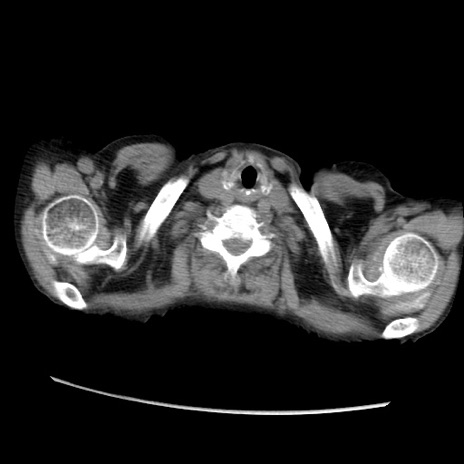

症例31(横断像)

【症例】80歳代 女性

【主訴】腹部膨満感

【現病歴】他院にて肝硬変にてフォロー中。1週間前から便秘、腹部膨満感、臍部腫瘤あり受診となる。

【既往歴】肝硬変

【身体所見】腹部膨隆あり、皮膚変化なし、疼痛なし。

【データ】WBC 4600、CRP 0.25